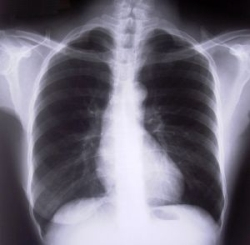

Zdroj:bigstockphoto.com

Rakovina pľúc

Ak pri vyšetrení pacienta vznikne podozrenie, že by mohlo ísť o rakovinu pľúc, robí sa röntgenové vyšetrenie hrudníka. Ak podozrenie pretrváva, nasleduje bronchoskopické vyšetrenie, pri ktorom sa za pomoci prístroja – bronchoskopu prezrú priedušky, prípadne sa dá odobrať materiál na cytologické a histologické vyšetrenie, a tieto môžu potvrdiť prítomnosť nádoru. Presný rozsah ochorenia sa stanovuje vyšetrením počítačovou tomografiou (CT), v komplikovanejších prípadoch sú k dispozícii ďalšie vyšetrenia ako pozitrónová emisná tomografia (PET), alebo magnetická rezonancia (MRI). Až po stanovení rozsahu ochorenia sa pristupuje k rozhodovaniu o optimálnom liečebnom postupe.